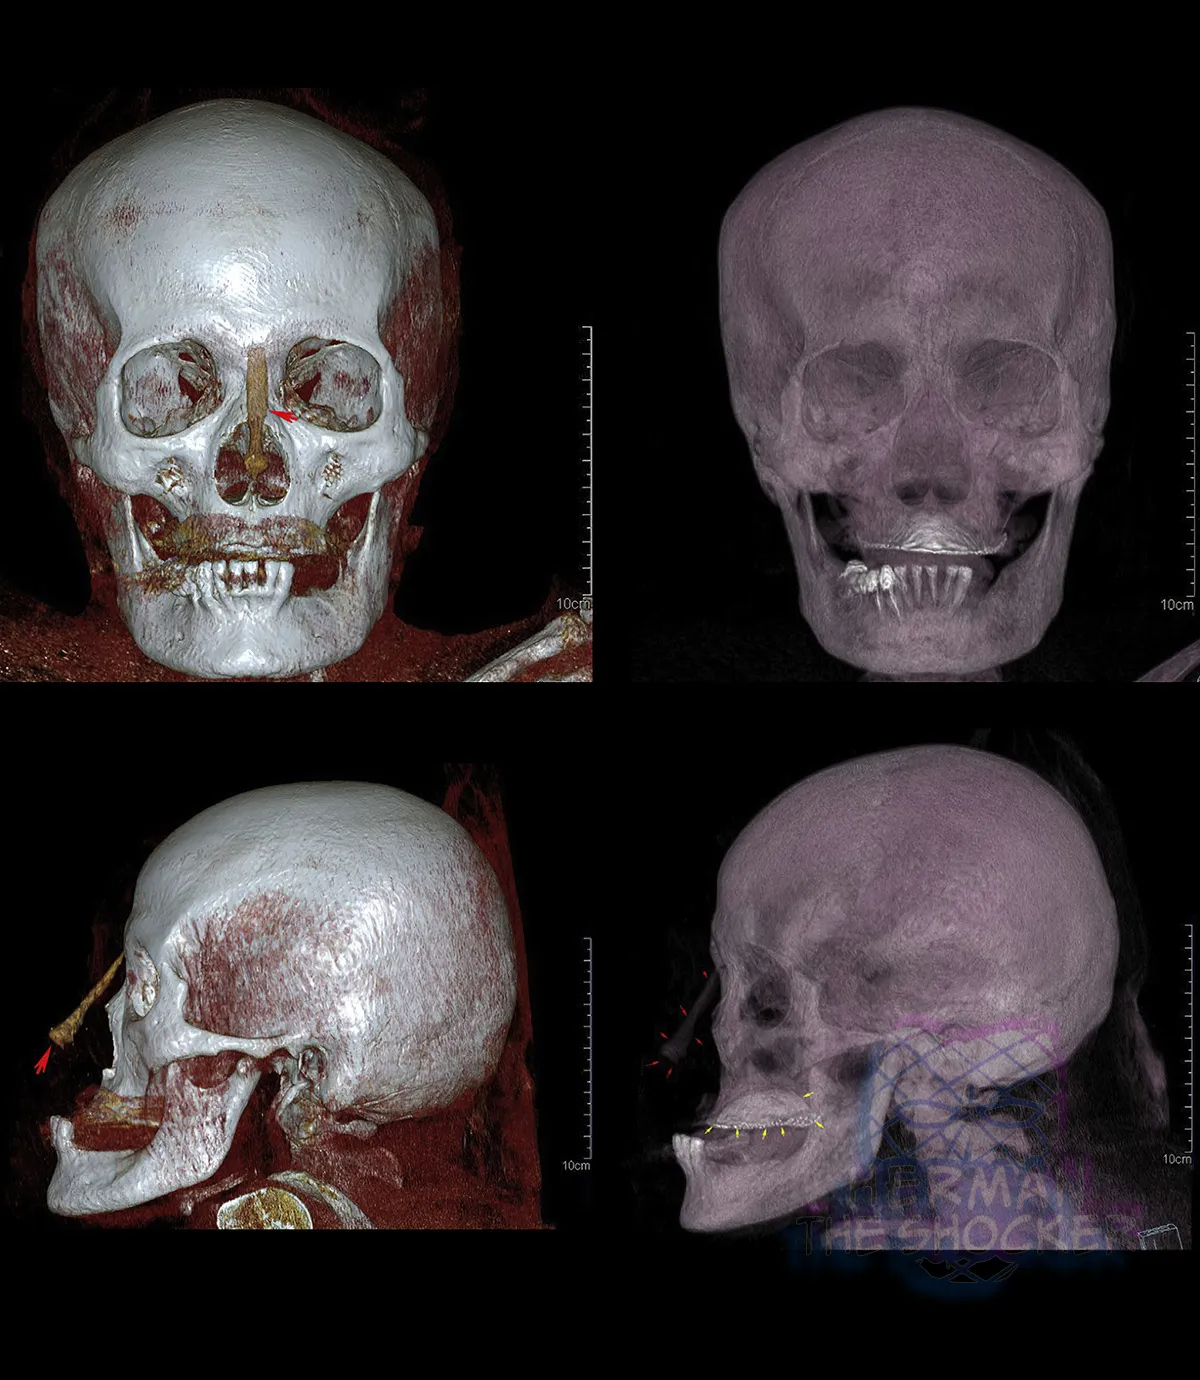

An elderly woman in a state of advanced decomposition

Australia. This elderly woman was located in a state of advanced decomposition. Because of decomposition the body was not visually identifiable. She was identified through x-ray comparisons.